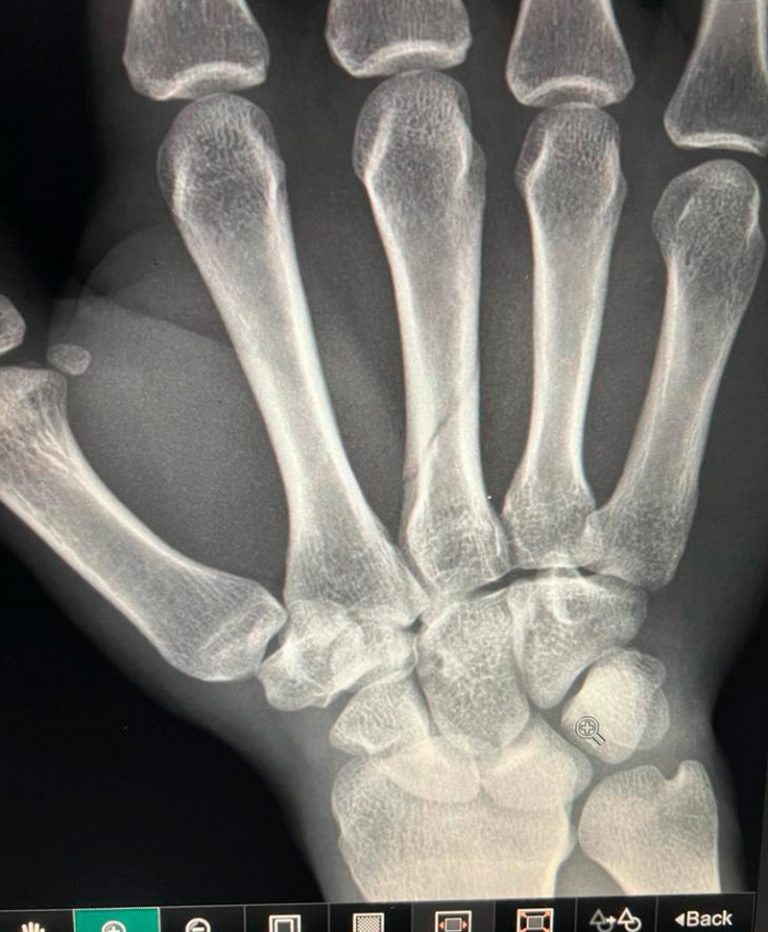

El diestro Fermín Espinosa “Armillita IV” sufrió un percance en la mano derecha en el momento de ejecutar la suerte suprema en el 6º toro del orden de lidia durante la corrida de toros de Feria en Arandas, Jalisco, siendo revisado por los servicios médicos de la plaza para después tomar camino a Aguascalientes para ser revisado por el Dr. David G. Martínez Robles, Servicio Médico de Las Plazas de Toros Aguascalientes resultando con una fractura del 3er metacarpiano de la mano derecha no desplazada.

Paciente de profesión torero el cual en la corrida de Arandas Jalisco el día de hoy 12 de Enero del 2024, en su segundo toro sexto de la lidia ordinaria, al entrar a matar sufre trauma contuso con la empuñadura de la espada sobre la palma de la mano derecha, presentando inmediatamente dolor intenso, inflamación severa e incapacidad para tomar la espada y muleta adecuadamente, por lo que es traído al Centro Hospitalario en Aguascalientes, donde se realizan radiografías de mano derecha, presentando fractura del 3er metacarpiano de la mano derecha no desplazada.

Necesitando muñequera corta para inmovilización, así como analgésicos y antiinflamatorios, fractura que tarda más de 15 días en sanar y no pone en peligro la vida